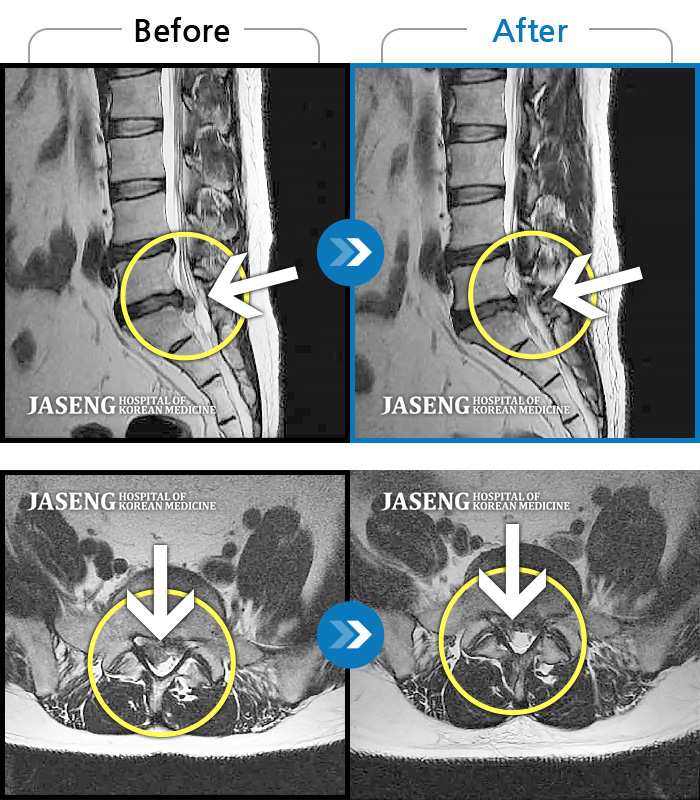

허리디스크

잠실 · 한상욱 원장

허리, 우측 엉치와 다리 후면 및 발끝까지 저림과 통증이 심하고 힘까지 빠진다.

촬영시기

2022.06.15 ~ 2022.11.11

2022.12.02